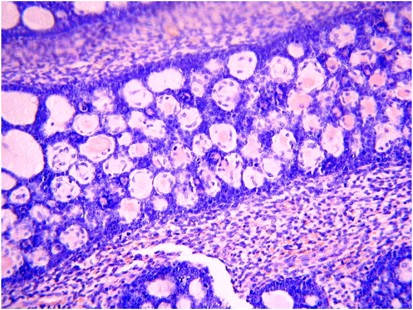

Histologically, the mixed nature of the tumour is exemplified by the presence of both epithelial and stromal elements, the latter predominating. At low power magnification, the tumour often has a phyllodes-like (leaf-like or club-like) architecture (Figure 7). The epithelial elements usually consist of glands, which may be dilated or slit-like with a phyllodes-like appearance, lined by cuboidal or low columnar cells. In most cases, the epithelium is endometrioid and resembles proliferative endometrium, although ciliated, mucinous and squamous epithelium may also be seen. Uncommonly, the epithelial component exhibits glandular complexity resembling atypical hyperplasia/endometrial intraepithelial neoplasia or carcinoma. The latter is usually a low-grade endometrioid carcinoma.28 The stromal component, which is typically low grade, is composed of spindled and/or round cells with scant cytoplasm, but rarely can be high grade. Intraglandular protrusions of stroma and the manner in which the stromal cells, which often resemble endometrial stromal cells, concentrate around or beneath the glandular elements (‘periglandular cuffing’) are characteristic (Figure 8). The ‘cuffing’ may be very thin (and thus overlooked) but is where nuclear atypia and mitotic activity are typically found (Figure 9). Although a mitotic rate of ≥2 per 10 high power fields (HPFs) is often seen, some tumours have a lower mitotic rate and should be diagnosed as adenosarcoma if the tumour has the characteristic aforementioned features as reflected in the 2014 WHO classification.1

Most adenosarcomas contain exclusively homologous mesenchymal elements, including smooth muscle with spindle or epithelioid morphology.38 Sex cord-like elements, composed of nests, cords, solid or hollow tubules, and identical to those seen in endometrial stromal neoplasms, may be present within the mesenchymal component; these may be positive for sex cord markers, such as inhibin and calretinin (Figure 10).40 The sex cord-like elements may contain abundant eosinophilic or foamy cytoplasm. Rarely, there is extensive overgrowth of sex cord-like elements within an adenosarcoma.41, 42 Approximately 25% of these tumours may contain heterologous stromal elements, most commonly rhabdomyoblasts and fetal-type cartilage, and rarely lipoblasts.40 The heterologous elements usually represent a minor component of the stroma, but are occasionally widespread. Extensive hyalinization, myxoid change or decidualization have been reported.41